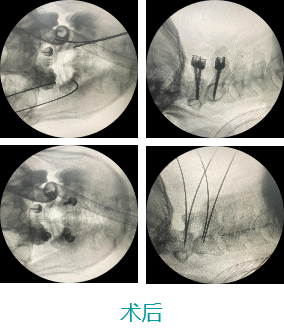

еӨ©зҺ‘IIи„ҠжҹұжүӢжңҜвҖ”йўҲжӨҺжүӢжңҜ

- дёӢдёҖзҜҮпјҡжӨҺй—ҙеӯ”й•ңйҖҡйҒ“е®ҡдҪҚ 2020-05-25